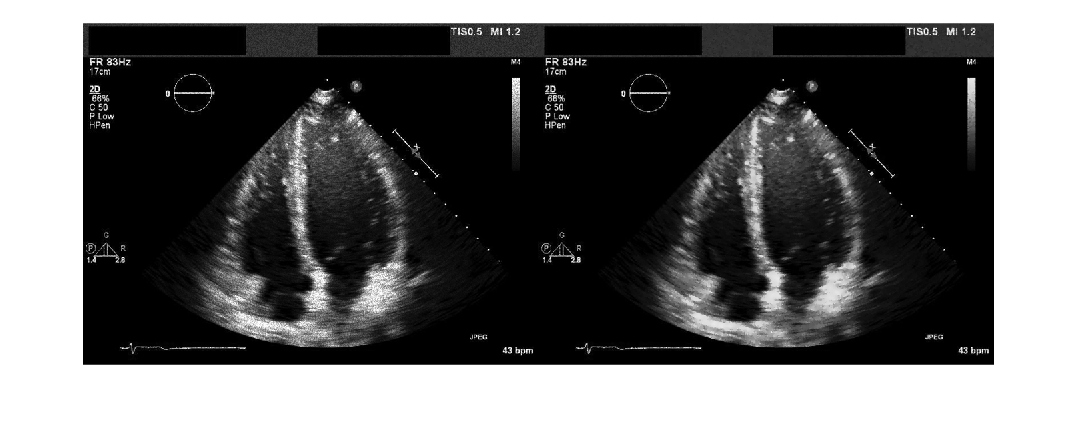

Coherent imaging modalities, such as ultrasound images, are prone to degradation

because of the interference of the transmitted waveform and its echoes. This degradation is

called speckle, and is a form of multiplicative noise. The

specklefilt function uses a speckle-reducing anisotropic diffusion (SRAD)

algorithm to reduce the speckle in an image.